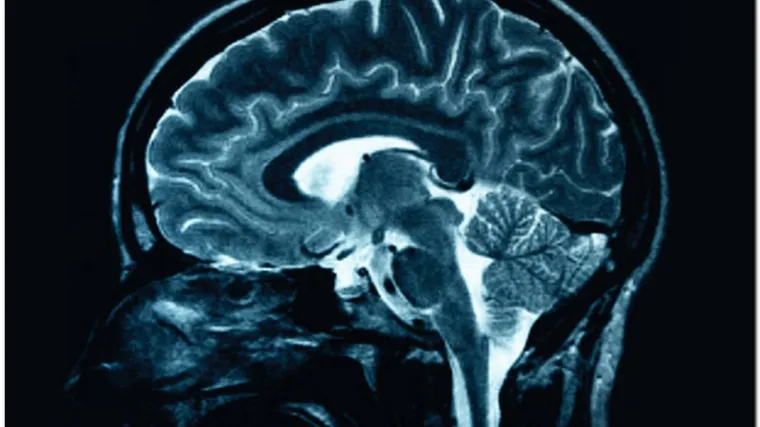

Doznali kako mogu hakirati u ljudski mozak!

Znanstvenik Stephen Hawking u fazi je testiranja revolucionarne naprave koja bi mu omogućila da komunicira preko moždanih valova. Stručnjaci su projekt ovog 70-godišnjaka koji pati od koji pati od amiotrofične lateralne skleroze i izgubio je moć govora prije skoro 30 godina, prozvali "hakiranjem u njegov mozak". Slavni znanstvenik koristi kompjuter za komunikaciju, ali sada gubi i tu sposobnost jer se njegovo zdravstveno stanje pogoršava. U suradnji sa znanstvenicima sa Sveučilišta Stanford zato radi na takozvanom iBrain -u, skreneru mozga koji mjeri električnu aktivnost, skuplja moždane valove i pretvara ih u komunikaciju putem kompjutera. "Tražimo način da zaobiđemo njegovo tijelo, odnosno da 'hakiramo' njegov mozak", kaže Philip Low, profesor i izumitelj iBraina.